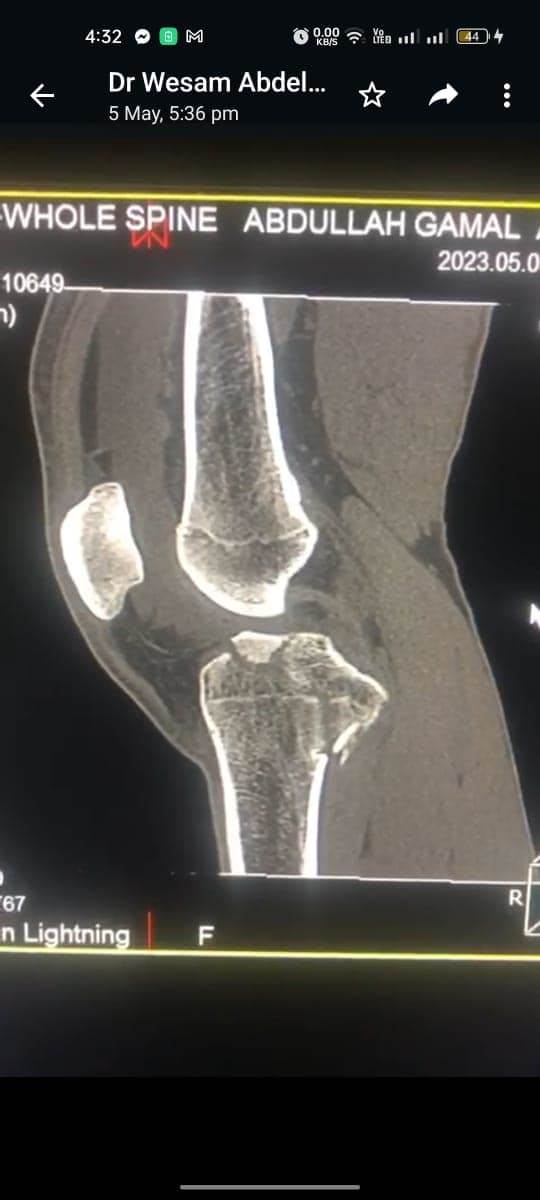

مشيرًا الى أن ذلك النوع من الكسور يكون قريبًا جدًا من الأعصاب والأوعية الدموية الرئيسية للساق والتي توجد خلف مفصل الركبة.. حيث تم الوصول الى الكسر وإعادة بناء سطح المفصل وتثبيته باستخدام شريحة ومسامير وأسلاك معدنية باستخدام جرح ٧ سنتيمترات خلف الركبة واستخدام مسامير جانبية مجوفة بدون فتح لتثبيت الجزء الخارجى من سطح المفصل، وتم الاطمئنان على الأوعية الدموية قبل إفاقة المريض، وبعد تمام الإفاقة.. تم الاطمئنان على الأعصاب والأوعية للمريض.

وأضاف أنه نظرًا لقرب هذا الكسر من سطح المفصل تم عمل أشعة مقطعية بعد الجراحة للتأكد من جودة بناء المفصل وعدم وجود أى بروز للمسامير داخل المفصل، وجارٍ تحضير المريض لعمل رنين مغناطيسى لتحديد الأربطة الداخلية والخارجية للركبة التي ستحتاج لإعادة بناء بالمنظار.